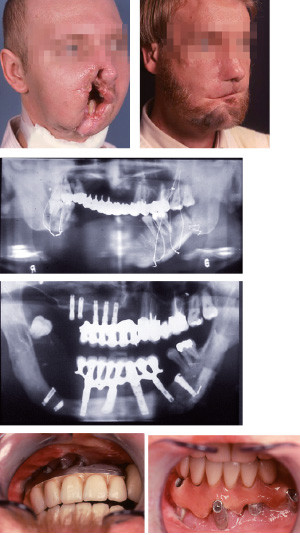

On peut affirmer qu’il y a un avant et un après Brånemark. Pour moi, le changement est survenu lorsque Jean-François Tulasne m’a proposé en 1983 de partir à Göteborg pour suivre un cours d’implantologie ; j’ai refusé catégoriquement, avant de me plonger dans la lecture des publications de l’équipe suédoise… et de changer d’avis. Six mois plus tard, après deux stages en Suède, nous posions nos premiers implants. Notre collaboration s’est étendue ensuite aux grandes reconstructions faites par Paul Tessier qui, pour la première fois, ont permis aux patients de retrouver des dents fixes (figures ci-contre). Per-Ingvar Brånemark eût mérité un Prix Nobel dans la recherche médicale, mais comme le veut l’adage, nul n’est prophète en son pays… Nous lui devons toute notre admiration et notre reconnaissance : il a complètement transformé notre profession.